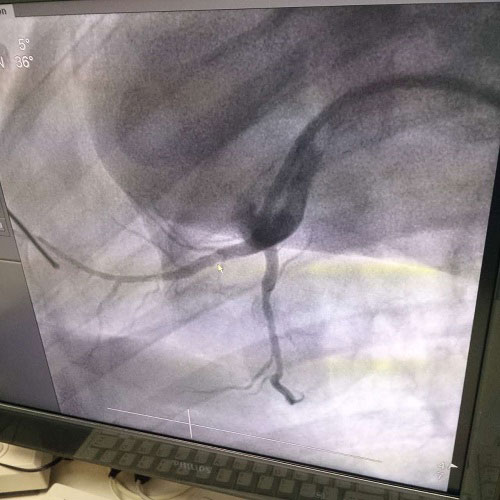

近年來(lái),隨著現(xiàn)代醫(yī)療技術(shù)的發(fā)展和醫(yī)療設(shè)備的日趨完善,介入性支架治療已經(jīng)成為介入心血管療法的一種主要手段。血管介入技術(shù)是在醫(yī)學(xué)影像設(shè)備的導(dǎo)引下,利用穿刺針、導(dǎo)絲、導(dǎo)管等器械經(jīng)血管途徑進(jìn)行診斷與治療的操作技術(shù),已經(jīng)成為治療各種危險(xiǎn)人類(lèi)健康疾病的最佳方法之一。

生物全降解鎂合金藥物洗脫支架是我由公司自主立項(xiàng)研發(fā)、主要工藝技術(shù)完全自主,具有完全自主知識(shí)產(chǎn)權(quán)。并且可行性強(qiáng),前期研發(fā)基礎(chǔ)扎實(shí),市場(chǎng)需求迫切,實(shí)施風(fēng)險(xiǎn)可控,屬全球同行業(yè)領(lǐng)先技術(shù),填補(bǔ)國(guó)內(nèi)技術(shù)發(fā)展空白,符合國(guó)家產(chǎn)業(yè)發(fā)展政策,社會(huì)、經(jīng)濟(jì)效益巨大。目前鎂合金藥物支架已進(jìn)入動(dòng)物實(shí)驗(yàn)階段,植入動(dòng)物體內(nèi)一個(gè)月之后效果良好。